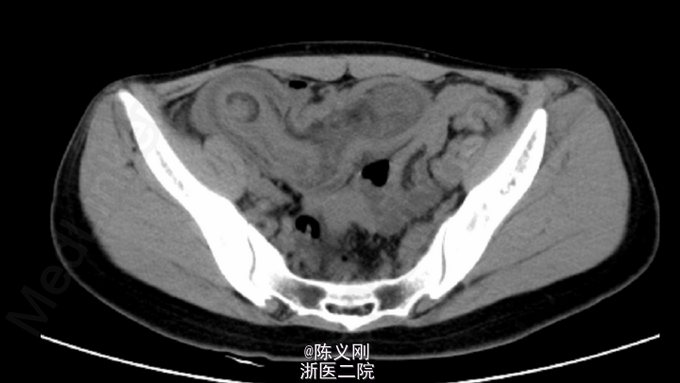

查体:中下腹压痛,右侧为主,无反跳痛,无肌紧张; 腹部平片:右下腹部升结肠、回盲部及部分小肠肠壁明显增厚、水肿,考虑炎症可能大,局部肠管套叠待排。 腹部CT:右下腹部升结肠、回盲部及部分小肠肠壁明显增厚、水肿,局部一段见靶环征。

诊断:肠套叠。 处理:急诊行“肠套叠复位+畸形小肠切除+肠重排+肠固定”,术中见:距回盲部可见长约80cm回肠套入升结肠,近端回肠肠管充血、水肿并扩张,余肠管未见明显穿孔、肿瘤及梗阻。将回肠手法复位后,可见距回盲部约70cm处一长约8cm垂直于回肠的畸形小肠,予以切割闭合器离断畸形小肠,于距回盲部取回肠及升结肠各10cm并排缝合固定。 术后予百定5.0g静滴bid抗感染,余吸氧、心电监护、护胃、化痰、补液等对症支持治疗。注意监测生命体征及腹腔引流情况。